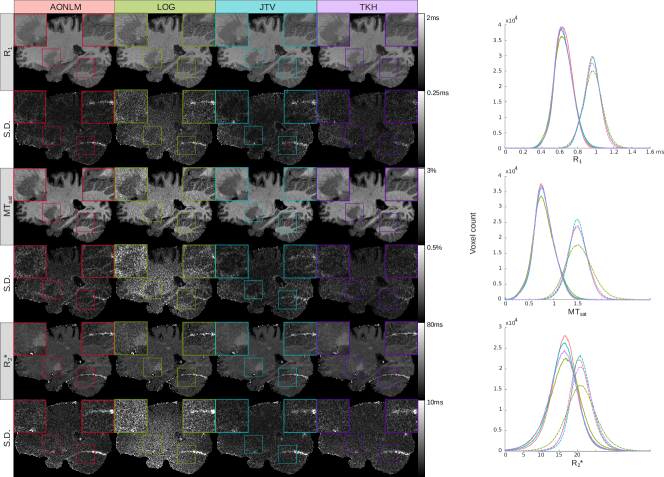

Quantitative Maps. R1subscript𝑅1R_{1}, MTsat and R2superscriptsubscript𝑅2R_{2}^{\star} maps reconstructed with each method are shown in Fig. 2, along with mean intensity histograms within GM and WM. Note that these maps are displayed for qualitative purposes; low standard deviations are biased toward over-regularised methods and do not necessarily indicate a better predictive performance. It is evident from the histograms that all denoising methods sharpen the peaks without introducing apparent bias. It can be seen that JTV has lower variance than AONLM in the centre of the brain and higher in the periphery. This is because in our probabilistic setting, there is a natural balance between the prior and the quality of the data. In the centre of the brain, the SNR is lower than in the periphery, which gives more weight to the prior and induces a smoother estimate. The mean standard deviation of AONLM, LOG, JTV and TKH is respectively 9.5, 11.5, 11.5, 9.9 ×103absentsuperscript103\times 10^{-3} in the GM and 8.6, 12, 9.6, 10 ×103absentsuperscript103\times 10^{-3} in the WM for R1subscript𝑅1R_{1}, 15, 2, 17, 20 in the GM and 11, 20, 10, 13 in the WM for R2superscriptsubscript𝑅2R_{2}^{\star}, and 4.6, 5.8, 5.1, 4.5 ×102absentsuperscript102\times 10^{-2} in the GM and 4.9, 8.2, 4.3, 4.7 ×102absentsuperscript102\times 10^{-2} in the WM for MTsat. Once again, variance is reduced by all denoising methods compared to the nonregularised loglinear fit. Again, a lower variance does not necessarily indicate a better (predictive) fit, which can only be assessed by the CV approach proposed above.

Figure 2: Quantitative maps. Left: example R1subscript𝑅1R_{1}, MTsat and R2superscriptsubscript𝑅2R_{2}^{\star} maps obtained with each method, and standard deviation (S.D.) maps computed across runs. Right: mean intensity histograms computed within the GM (plain) and WM (dotted) masks.